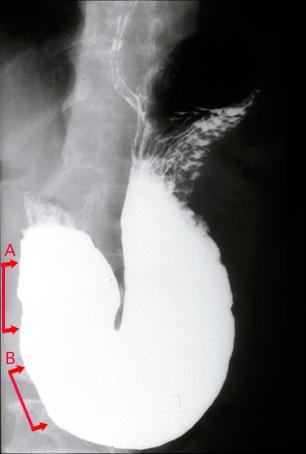

疾病(病理主体)的分类恶性淋巴系统・血液系统肿瘤/ATL (成人,ATL细胞白血病)

检查方法X线

肿瘤的肉眼分类0型(表在型)/IIa型(IIa+IIc)

肿瘤最大直径20~24

肿瘤的深度sm

多发性肿瘤(同一器官)有(同时性)

多重性肿瘤(多个器官)有(同时性)